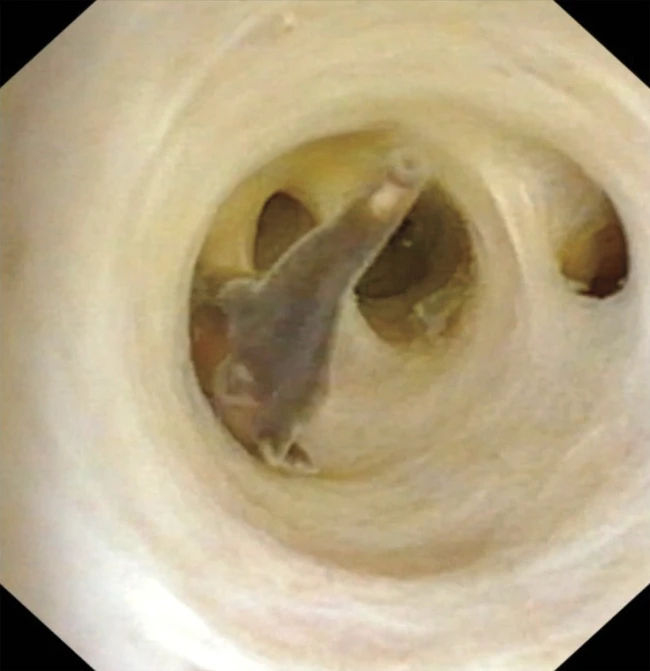

Cu ajutorul unei mici camere de luat vederi introduse în abdomenul bărbatului de 70 de ani - care urma să fie supus unei intervenții chirurgicale pentru a îndepărta o tumoare în vederea tratării cancerului de colon - medicii au descoperit cinci viermi paraziți mari, de culoare maro, în tractul biliar, ansamblul de organe și tuburi de legătură pe care organismul îl folosește pentru a produce, stoca și secreta bila - un lichid galben-verzui care ajută la digestia grăsimilor.

Medicii au extras creaturile și le-au identificat ca fiind Clonorchis sinensis. Medicii au publicat detalii despre descoperirea lor pe 28 decembrie în New England Journal of Medicine.

În mod normal, medicii diagnostichează infecția cu C. sinensis după ce identifică ouăle parazitului în scaunul pacientului. Cu toate acestea, în acest caz nu au fost găsite ouă. În schimb, bărbatul a fost supus unei proceduri medicale numite colangioscopie, în cadrul căreia medicii folosesc un tub lung și subțire cu o cameră în interior pentru a examina tractul biliar.

Ulterior, medicii plănuiau să efectueze o intervenție chirurgicală pentru a-i îndepărta tumora și vezica biliară, când au avut o surpriză. Ei au îndepărtat apoi toți viermii și i-au prescris medicamente antiparazitare pentru a elimina infecția. De asemenea, a început un tratament de chimioterapie pentru a trata cancerul din intestinul gros.